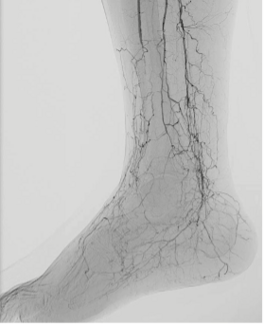

The authors outline the clinical burden of CLTI, explain the LimFlow procedure, and review evidence from the CLariTI and PROMISE studies supporting its use in "no-option" patients.